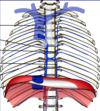

Q

CN:

What is a coronary bypass graft?

A

A procedure to bypass a blocked section of a coronary artery and to deliver oxygen to the heart